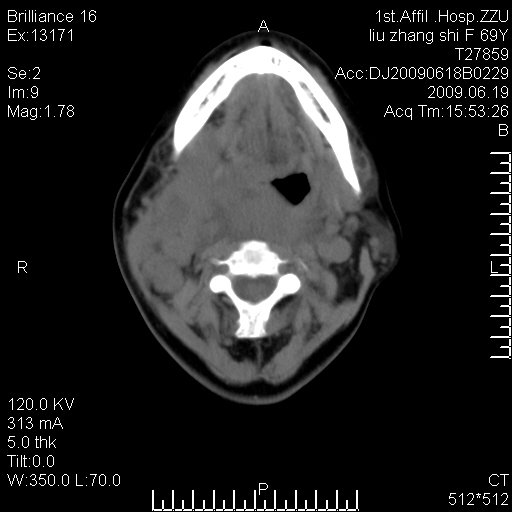

标题: CT26782:女,69岁,颈部占位,3天后公布病理结果。

【病理证实系列】女,69岁,颈部占位,有病理结果,3天后公布。(由于病例时间较久,临床资料不全,请网友见谅)本系列将有几百种常见、少见及罕见病例,均经病理证实。病例资料来自郑州大学第一附属医院。与网友共享,本人有空就发。

甲状腺癌并颈部淋巴结转移。感谢楼主的良苦用心,谢谢。

甲状腺癌并颈部淋巴结转移。

需与鼻咽癌鉴别!

支持甲状腺癌广泛侵及周围结构并颈部淋巴结转移。

鉴别:淋巴瘤、恶性神经源性病变、恶性纤维组织细胞瘤。

病理结果:颈部非霍奇金淋巴瘤。